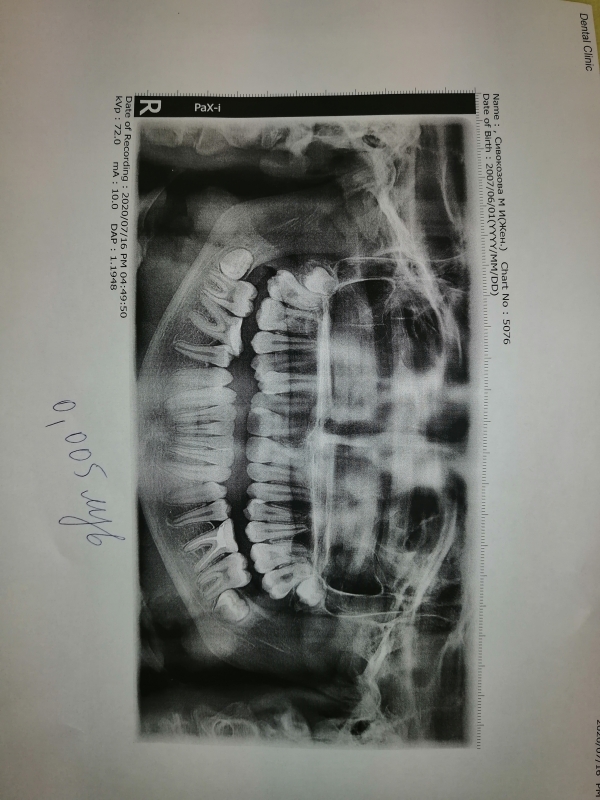

По ортопантомограмме судить о необходимости челюстно-лицевой операции невозможно.

Есть определённые критерии, позволяющие проводит компромиссное лечение, но для этого требуется тщательная диагностика.